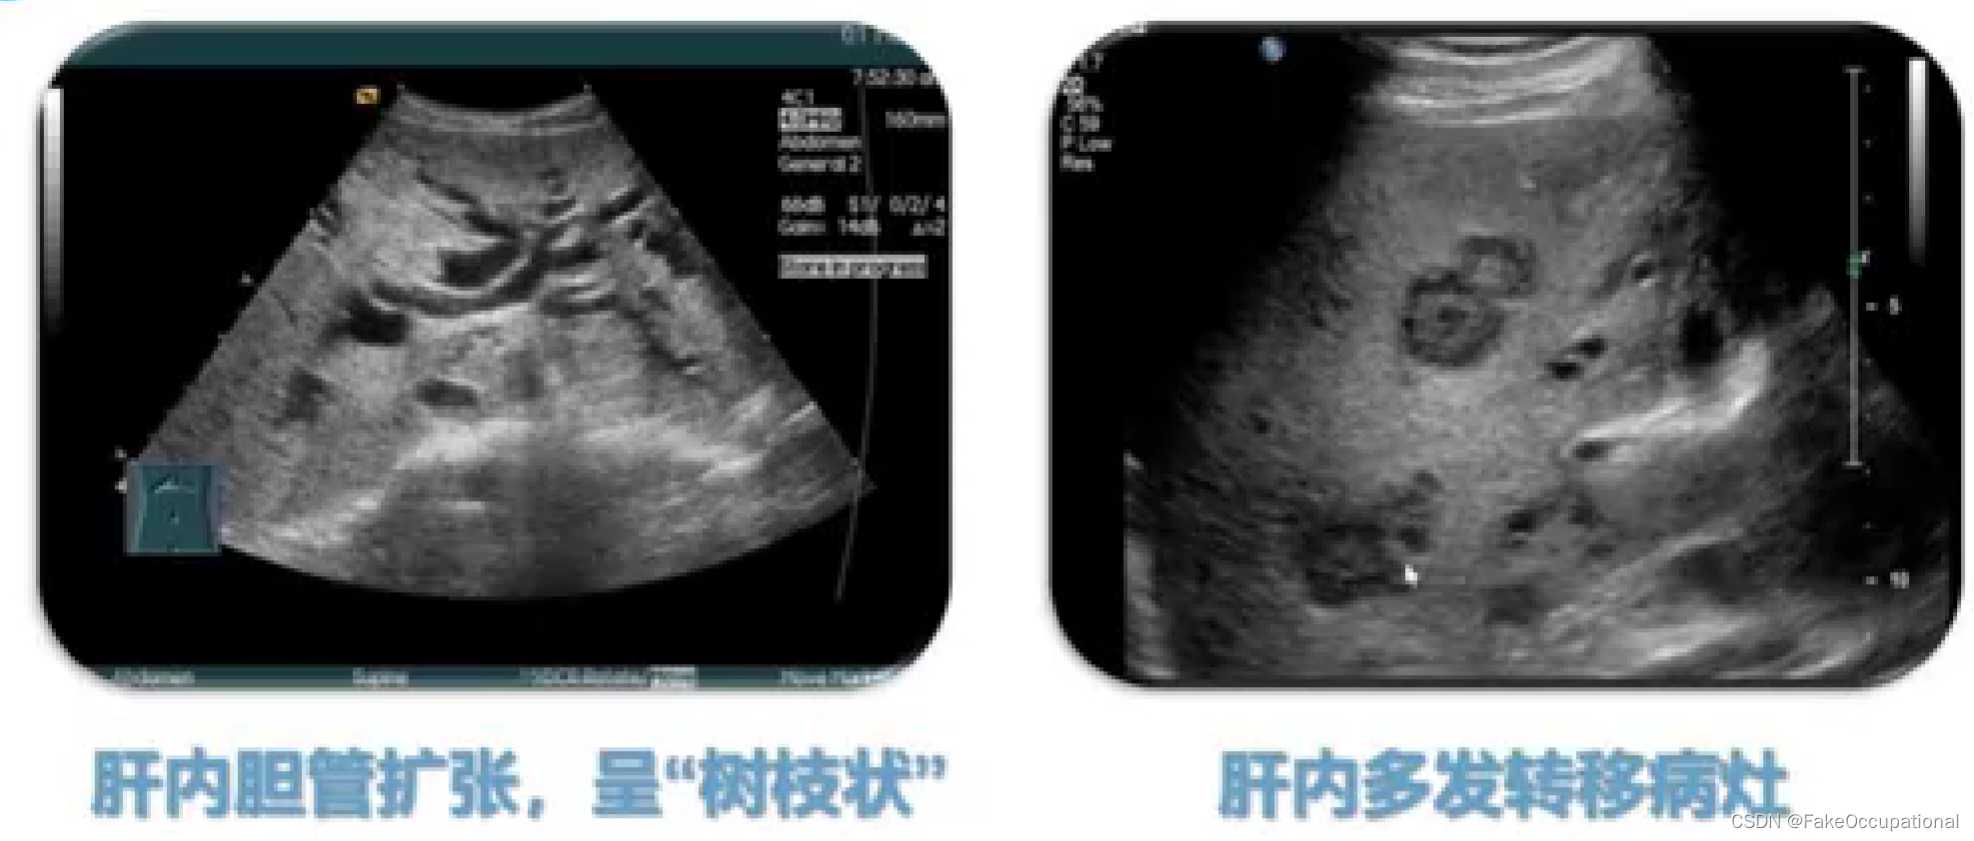

超声声像图: - 肝外胆道不同程度扩张

- (五)阻塞性黄疸的鉴别诊断

黄疽:血清内胆红素浓度增高。引起巩膜、皮肤、粘膜、体液、其他组织的黄染

临床分型:肝前性黄疸(溶血性黄痘、非溶血性)、肝性黄痘及肝后性黄疸(阻寒性黄疸)